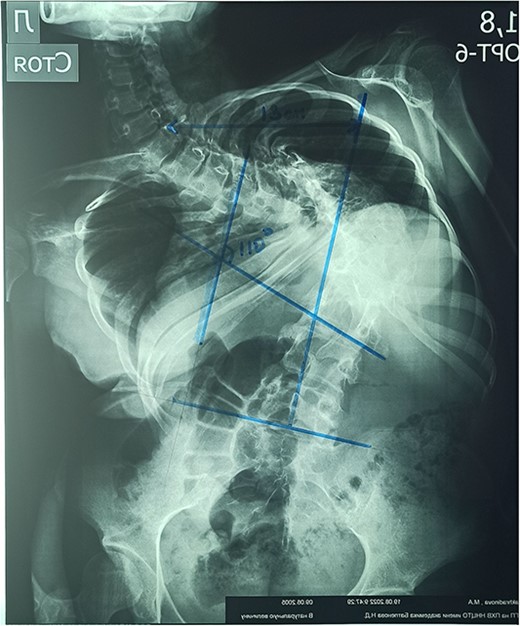

On the preoperative anterior–posterior X-ray, the Cobb angle was 110°; violation of frontal balance—13 cm (Fig. 2).